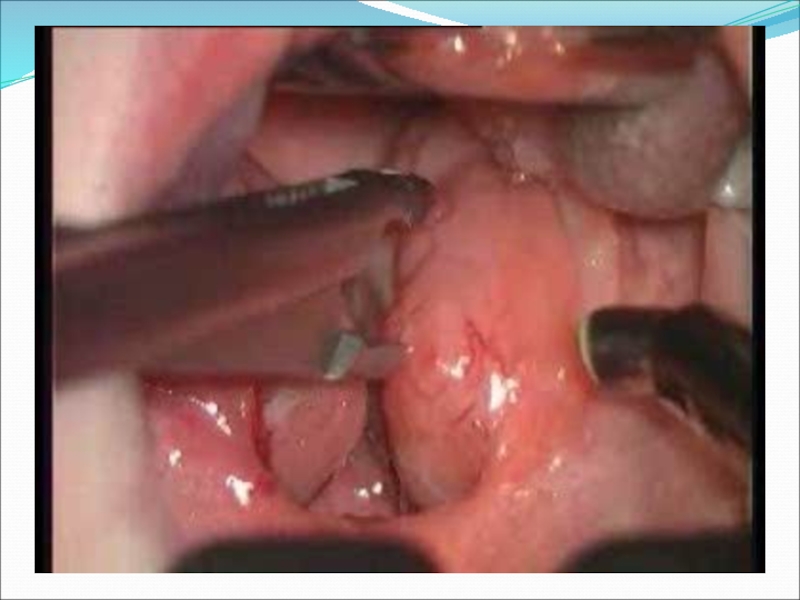

Слайд 39Лигирование клинонебной артерии

Собственно резекция опухоли начиная от крылонебной ямки

Лигирование клинонебной артерииСобственно резекция опухоли начиная от крылонебной ямки